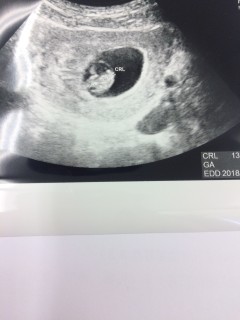

体外受精の新鮮胚移植1回目での妊娠です。 不妊治療専門クリニックから 本日産院に転院しました。 前回8wで確認済みの心拍が止まってしまったので 毎日不安で過ごしながらも こちらのみなさんのエコー画像参考にさせていただいてました。 今日は心音も聞く事が出来て一安心です。 このまま元気に育ってくれますように!!

最初の受診から2週間後。期待と不安が半分半分の2週間でした。無事赤ちゃんと心拍確認できました。「元気に動いてますよ」と先生に言ってもらえました。一安心。また2週間後の受診も元気に成長していてほしいです。CRL11.1mm